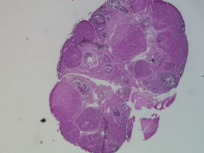

Genus: Mus (mice)

Species: Mus musculus ()

Life Stage: prepubertal

Age: 0 years, 25 days

Accession #: MDB0000580

Ovary position: unspecified

Location: wholeOvary

Section thickness: 5 microns

Fixation: neutralBufferedFormalin10

Stain: Hematoxylin and Eosin

Immunohistochemistry: None

Experimental treatment: Control - mock treatment - PBS, IP injection, 5 days

Other pathology: None